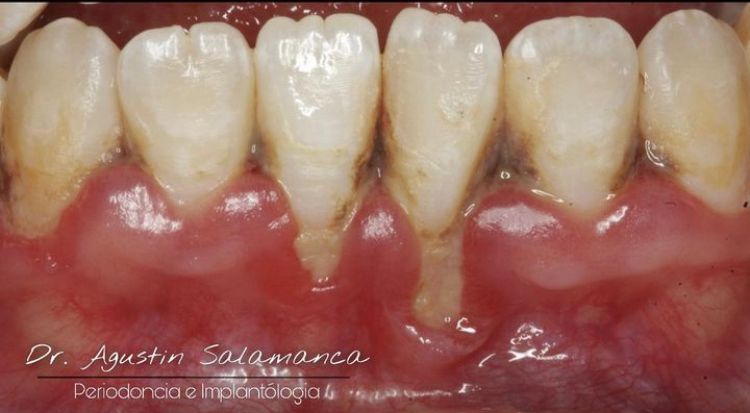

La enfermedad periodontal es una patología infecciosa, inflamatoria crónica, de origen bacteriano causada por una comunidad de microorganismos llamada biofilm dental que se adhieren a los dientes, provocando una respuesta inmunitaria que afecta a los tejidos que soportan al diente como el hueso alveolar, ligamento periodontal, cemento radicular. Si esta enfermedad no se controla nos lleva a la primera patología llamada gingivitis con signos clínicos inflamación, sangrado, enrojecimiento en las encías sin perdida ósea. Y si esta no se controla se asevera con presencia de periodontitis con signos clínicos de inflación, dolor, perdida de los tejidos de soportan al diente.